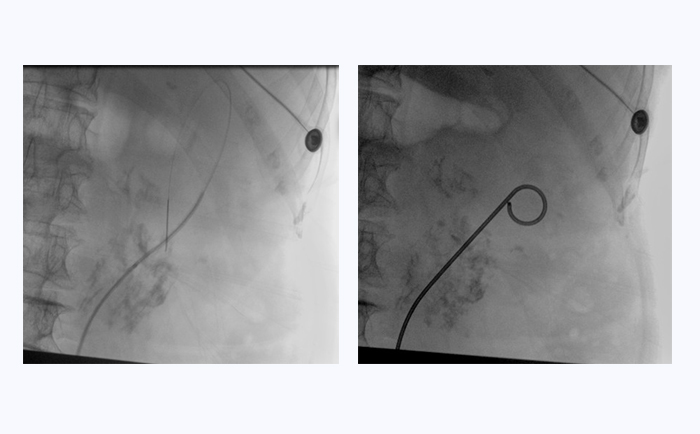

患者采用結(jié)石位進(jìn)行該手術(shù)。全麻后,操作輸尿管鏡從尿道進(jìn)入膀胱,通過鏡下觀察,找到輸尿管開口。此時(shí),在普愛醫(yī)療大平板一體式C形臂透視引導(dǎo)下,穿入導(dǎo)絲,到達(dá)腎盂并確認(rèn)位置,同時(shí)配合輸尿管鏡,找到狹窄部位。接下來,同樣在透視引導(dǎo)下,沿導(dǎo)絲插入雙J管支架,當(dāng)支架兩端到達(dá)相應(yīng)位置后,抽出導(dǎo)絲和輸尿管鏡,完成手術(shù)。

普愛醫(yī)療大平板一體式C形臂臨床圖像